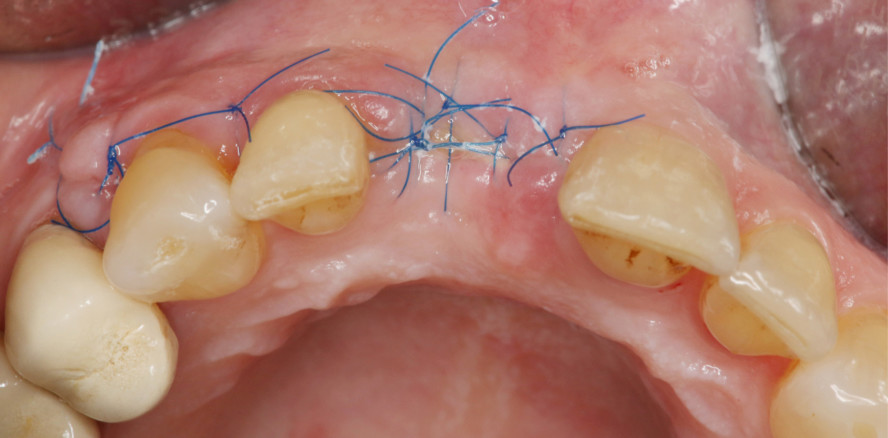

Foto: © Dr. Frederic Kauffmann

Hyaluronsäure (HA) ist ein natürlicher Bestandteil des Bindegewebes und hat die Eigenschaft, Flüssigkeiten in großen Mengen zu speichern.1 So ist HA am gesamten Prozess der Wundheilung beteiligt.2,3 Die Anwendung von HA stimuliert die Neoangiogenese nach Eingriffen und beschleunigt so den Heilungsprozess erheblich.4,5 Moderne Hyaluronsäure wird, ähnlich wie Insulin, durch Bakterienfermentierung hergestellt. Dies gewährleistet, dass HA frei von tierischen Eiweißen ist.6,7 So gibt es bislang keine Berichte über direkte Nebenwirkungen auf Hyaluronsäure in der dentalen Anwendung. Insbesondere moderat vernetzte Hyaluronsäure (xHyA, hyaDENT BG, REGEDENT GmbH) mit längerem Resorptionsprofil von mehreren Wochen eignet sich für den Einsatz bei parodontalen Anwendungen sowie für knöcherne Augmentationen oder Weichgewebskorrekturen wie Rezessionsdeckungen. Hierbei unterstützt die entzündungshemmende und antimikrobielle Wirkung1 den Heilungsverlauf.

Bei chirurgischer Anwendung kann vernetzte Hyaluronsäure zu einer echten parodontalen Regeneration und nicht nur zu einer bindegewebigen Auffüllung der Tasche führen.9 Erwähnenswert ist die vereinfachte Anwendung: die eingebrachte Hyaluronsäure zieht Flüssigkeiten wie Blut an und stabilisiert das entstehende Koagel; dies ist ohne vorherige Wurzelkonditionierung oder Trocknung der Wurzeloberfläche möglich.